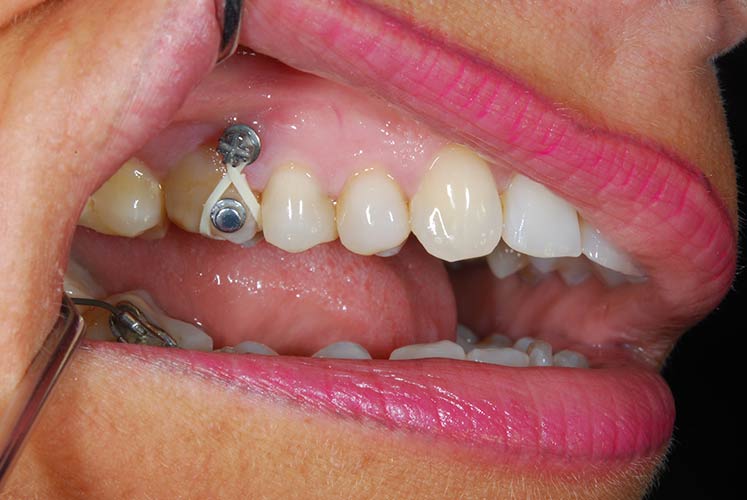

Trattamento ortodontico nell'adulto con intrusione del I° molare superiore mediante l'utilizzo di mini impianti

Durata del trattamento: un anno